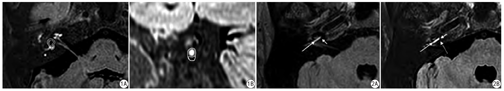

采用双盲法由2名三年以上放射诊断工作经验住院医师进行图像分析,经讨论达成一致性意见。利用GE Healthcare Centricity PACS 4.0附带的AW Suit图像三维后处理工具,分别在3D FLAIR序列和3D real IR序列图像上多曲面重建方式重建出前庭面积最大切面及穿过窝轴的耳蜗底旋短轴位切面(图1)[8,9],在这两个切面分别测量29例受检者双侧前庭及耳蜗底旋内淋巴间隙占总淋巴间隙面积比值R(前庭为RV,耳蜗为RC) ,将2名医师分别测量的同一受检者每侧耳的RV、RC值(组内相关系数,ICC=0.891),取平均值得到最终的该受检者该侧耳的RV及RC值。由于3D FLAIR序列耳蜗区内淋巴间隙与骨壁结构分界不清,无法清晰勾画内淋巴间隙与骨壁的边界从而无法准确计算内淋巴间隙面积,因此需借助3D T2WI DRIVE序列测得相应切面内外淋巴间隙总面积(内外淋巴间隙均呈高信号),用该总面积减去3D FLAIR序列所测得耳蜗外淋巴间隙面积即为内淋巴间隙面积,从而测得3D FLAIR序列耳蜗底旋内淋巴间隙与总淋巴间隙比值RC。而3D FLAIR序列前庭区、3D real IR序列耳蜗及前庭区内、外淋巴间隙边界均可清晰勾画,可直接在3D FLAIR序列和3D real IR序列图上测得相应的RV及RC值。参照2009年Nakashima等[10]提出的标准:前庭区内淋巴积水程度分为3级,0级(无内淋巴积水,R≤1/3),1级(轻度积水,1/3<R≤1/2),2级(严重积水,R>1/2) ;耳蜗区内淋巴积水程度亦分为3级,0级(无内淋巴积水,无前庭膜移位),1级(轻度积水,前庭膜移位但内淋巴间隙面积不超过前庭阶面积),2级(严重积水,前庭膜移位且内淋巴间隙面积超过前庭阶面积)。按照该标准评估前庭及耳蜗区内淋巴积水程度分级值G(前庭为GV,耳蜗为GC)。根据临床诊断,提取29位受检者共计41只患侧耳在3D FLAIR序列和3D real IR序列图像分别获得的RV、RC、GV、GC值,并纳入统计分析。3D T2WI DRIVE序列除了辅助3D FLAIR序列测量耳蜗区RC值外,还用以排除脑内、桥小脑角区的病变。

本研究结果中,3D real IR序列测得的患侧内耳前庭及耳蜗底旋区RV及RC值均大于3D FLAIR序列测得值,这表明在客观的定量分析方面,3D real IR序列更容易发现内耳的内淋巴积水。其次,3D real IR序列测得的GV、GC≥1级的患耳占比高于3D FLAIR序列,表明在相对主观的定性分析方面,3D real IR序列对于MD内淋巴积水的发现率高于3D FLAIR序列,尤其是耳蜗区3D real IR序列诊断出内淋巴积水的患耳占比约39%(16/41),而3D FLAIR序列却只有12% (5/41),提高了MRI内耳淋巴造影对耳蜗区内淋巴积水的诊断能力。此结果的呈现主要是因为3D real IR序列具有更好的组织分辨率,它采用"real"重建模式的反转恢复TSE序列,此重建模式能够使IR序列反映组织的真实正负信号值而非绝对值,选择合适的TI (1650 ms)值可使图像上内淋巴间隙显示为低信号(负值),外淋巴间隙显示为高信号(正值),周围骨质显示为等信号(接近0),因此能够通过一次扫描将内、外淋巴间隙及周围的骨质区分开;而3D FLAIR序列中只能区分内耳内淋巴间隙(呈低信号)与外淋巴间隙(呈高信号),但不能区分内淋巴间隙与周围骨质边界(两者均呈低信号),尤其是耳蜗区(图2)[6,7]。然而,3D real IR序列虽然拥有更高的组织分辨率,在显示内淋巴积水时有较大的优势,但在国内临床工作中一直未得到普及,主要因为既往文献[6,7]报道的3D real IR序列的扫描时间较长,一般在14~15 min,而国内人口多,相应患者多,单个患者检查时间不能过长,否则不利于临床工作的开展。在本研究中,在保证图像诊断质量的前提下,通过对该序列参数的优化,本研究中3D real IR序列扫描时间缩短至7 min 14 s,可以作为常规应用于临床MD的诊断。相信随着MRI技术的发展,其3D real IR的扫描速度将会得到更进一步提升,更加有利于作为MD的常规影像学检查技术加以推广。